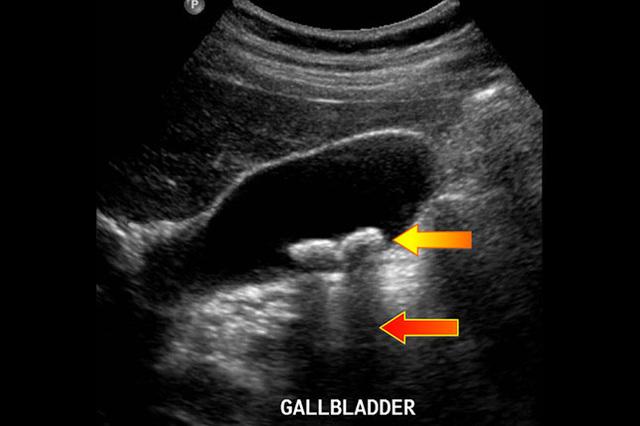

我让患者去做个上腹彩超看看,果然,彩超提示胆囊炎,并且可以看到胆囊内多发结石。

嘱护士给患者应用了一支解痉止痛的药物后,患者腹痛有明显的减轻,我告诉患者及家属,你这个属于胆囊多发结石,并发急性胆囊炎,建议先行给予抗炎对症治疗,然后近期安排手术,行胆囊切除术。